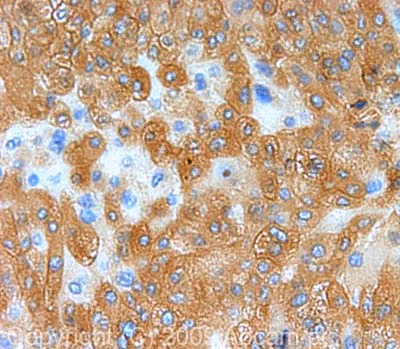

Immunohistochemistry (Formalin/PFA-fixed paraffin-embedded sections) - Anti-Peroxiredoxin 1/PAG antibody (AB41906)

IHC image of Peroxiredoxin 1/PAG staining in human liver carcinoma FFPE section, performed on a BondTM system using the standard protocol F. The section was pre-treated using heat mediated antigen retrieval with sodium citrate buffer (pH6, epitope retrieval solution 1) for 20 mins. The section was then incubated with ab41906, 1μg/ml, for 15 mins at room temperature and detected using an HRP conjugated compact polymer system. DAB was used as the chromogen. The section was then counterstained with haematoxylin and mounted with DPX.